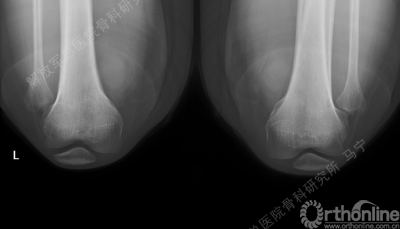

虽然是软骨损伤,但也需要X线评估关节结构,测量双下肢力线,髌骨轨迹,Q角等,排除结构因素引起的软骨损伤,若术前存在发育不良,脱位,半月板损伤,交叉韧带损伤,必须先进行矫形,最后再进行软骨修补,才能达到最佳效果和持久性。

双侧髌骨软骨同时损伤,同时做的软骨移植,双侧同时做目前在技术上没有问题,但术后康复起来会比只做单侧要时间长一些。